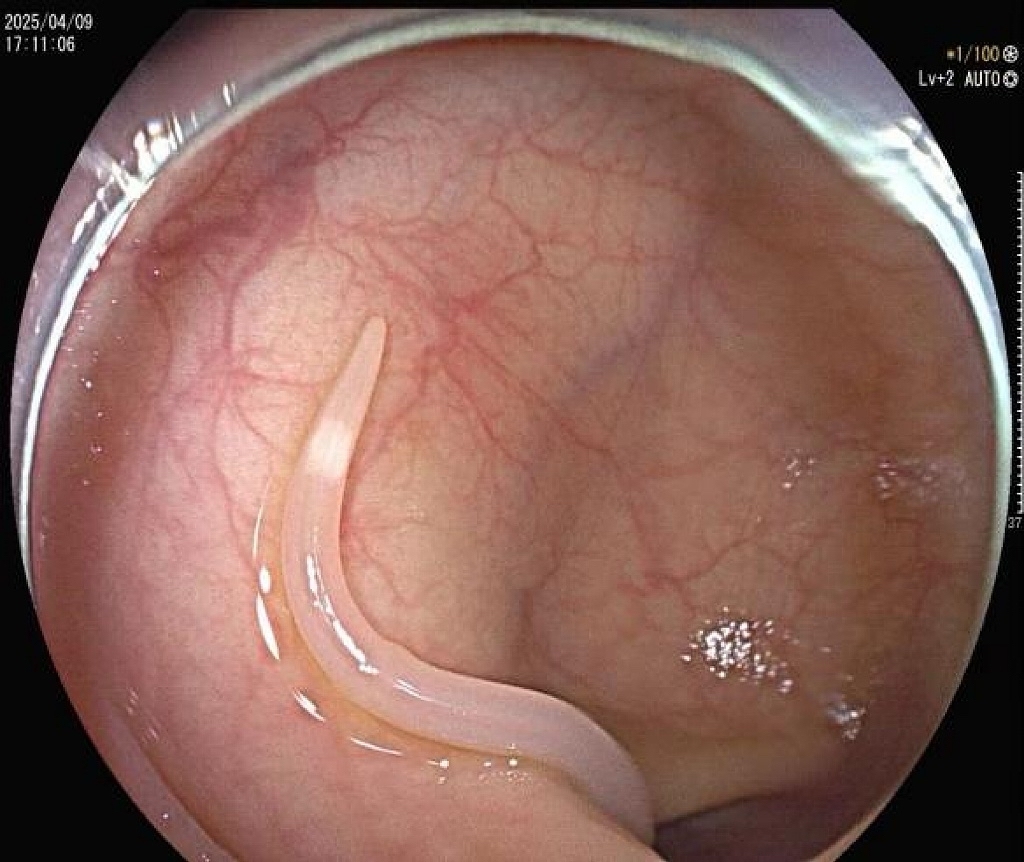

金女士(化名)近半年来反复出现下腹绞痛,自行服用药物后未见缓解。到广州中医药大学深圳医院内分泌科门诊就诊,接诊医师刘畅在细致问诊和体格检查后,初步排除了肠胃炎等常见病因,果断为她安排了胃肠镜检查。经脾胃病科医师刘乐鑫肠镜检查,发现她的肠道内竟然有一条白色细长的“小虫子”在慢慢蠕动,原来是一条活体寄生虫,医师果断通过肠镜用活检钳夹住蛔虫,慢慢将它从肠道里拖了出来。经检测,该寄生虫为蛔虫,食用被虫卵感染后的食物有可能导致肚子里长蛔虫。

(2)胃肠镜检查:胃肠镜检查时能在十二指肠、盲肠、乙状结肠、直肠等部位可直接观察到活的虫体,尤其适用于反复腹痛、常规检测阴性患者,还能使用活检钳将虫体夹出送去检验进行判断,为诊断和治疗提供有力证据。

2.内镜治疗:如本例患者通过肠镜直接取虫,可快速“缉拿真凶”。